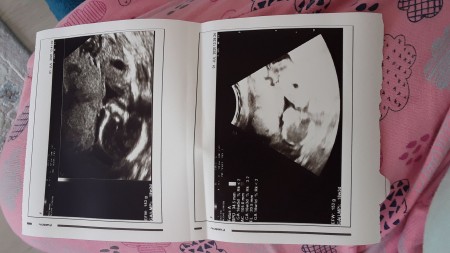

Kızlar az önce doktordan geldim 12 haftalikken doktorum kemik yapısına göre %80 erkek demişti şimdi 16 haftalık olduk doktor önce kıza benziyor dedi hemen ardından pipi gördüm dedi ilk defa ikilemde kalan doktor gördüm sonra da emin değilim dedi kesti attı bende şaşırdım acaba beni mi geçiştirdi böyle Bisey yaşayan oldu mu

image

Canım senin bu  attigin   18 haftalik  bir foto  demi   yoksa 16    galiba    bende büyütün bugün  hastanedeydim yoğundum   iyce  bakamadım   telefona  çektim büyütüp  baktım  o plessentami yoksa çıkıntını ikilemde kaldım  glsjba erkek şimdi fikrim öyle  iyce bakınca  çıkıntı  var gibi

Sağlıkla al  inş  Öğrenin ce yazarsın  canım  kız  erkeğe  dönmez  ama  erkek kiza dine bilir  cunki  plesen ta ile  karıştırılıyor   net bakınca erkek  oldugnu düşündürdü

16+1 haftalık kuzum sen hemşire falan mısın